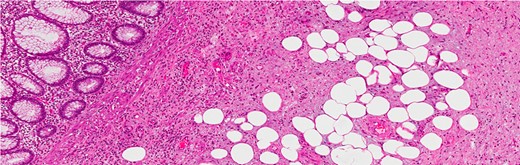

Histological examination showed an appendix measuring 7 cm in length and 0.8 cm in diameter with a cystic lesion at the base measuring 3.5 × 2.5 cm2. It had a grey homogenous cut surface invading the appendix wall while the mucosa was unremarkable. The mucosal lining showed elongated and dilated tubules with Goblet cell proliferation with no evidence of dysplasia. The sub-mucosa displayed an area of extensive edema, vascular congestion with focal hemorrhage and abundance of spindle cells, dispersed in a loose fibromyxoid stroma. The sub-mucosal background had copious eosinophils, lymphocytes and blood cells. There was no mitosis, acute inflammation, granuloma, ischemia or vasculitis (Figs 3–6). These findings are consistent with an appendicular IFP (Vanek’s tumor).

The tip and the middle part of the appendix with no specific pathology (H&E stain, low power).

The base of the appendix with the mass (H&E stain, low power).

(a) H&E stain of a lesion in the appendiceal wall with infiltrative nature (intermediate power). (b) H&E stain of abundant spindle cell, dispersed in loss fibromyxoid stroma, infiltrating the fat (high power).

Infiltration into the sub-mucosa of the appendix (H&E stain, high power).